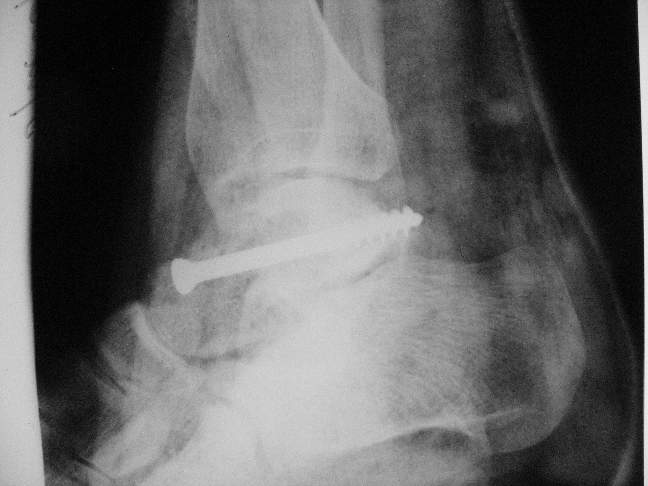

Здесь на фото примеры:

Переломовывих тарана с повреждением медиальной стороны. Через 4 часа после

поступления проведена репозиция и фиксация тарана после

Irrigation&Debridment. Частичное несращение медиальной лодыжки не беспокоит,

вернулся к активному образу жизни. Полная нагрузка разрешена через 11

недель. Финальные снимки через 11 месяцев.